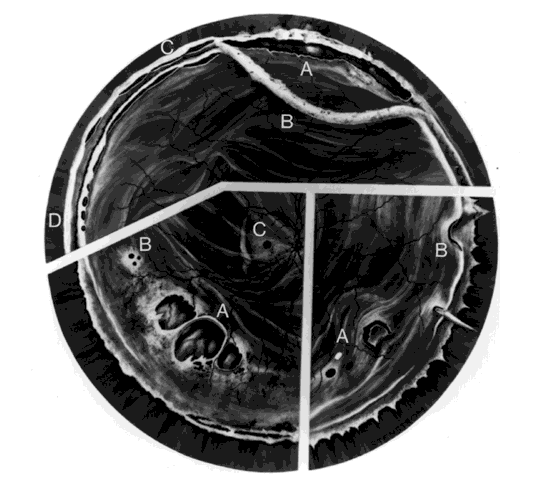

hemorrhage, retinal breaks, and retinal detachment. SUBLUXATION OR DISLOCATION OF THE LENS Minor degrees of subluxation should be suspected when phakodonesis or iridodonesis is noted. Zonular rupture is certain if there is vitreous prolapse into the anterior chamber. In the absence of cataractous changes and related visual impairment, treatment is not indicated. A subluxated, cataractous lens can be removed by aspiration-irrigation or phacofragmentation through a limbal incision, but complications may occur, including posterior dislocation of the lens or lens fragments, vitreous prolapse and incarceration, and vitreous aspiration with resultant vitreous base traction and retinal tear formation. Also, visualization of the anterior vitreous by coaxial illumination is poor compared with fiberoptic endoillumination. These problems make pars plana lensectomy an attractive alternative. Bimanual techniques permit fixation and simultaneous removal of the lens by the vitreous suction-cutter, if the lens is soft, or phacofragmentation if it is sclerotic (Fig. 1A). Posteriorly dislocated fragments can be removed safely, with minimal vitreous traction, using the same incisions and instruments (see Fig. 1B). With endoillumination, prolapsed and juxtalenticular vitreous is readily identified and excised with the vitrectomy probe. Without question, pars plana lensectomy is the preferred method for removing a completely dislocated lens. The technical aspects of dislocated lens and lens fragment removal are described elsewhere in these volumes. VITREOUS HEMORRHAGE Blood in the vitreous may come from tears in the iris, ciliary body, choroid, or retina. Hemorrhage from choroidal ruptures accumulates beneath the neurosensory retina; it then passes through the retina into the vitreous without necessarily causing a retinal break. Regardless, it is important to assume that a retinal break is present until proved otherwise. Vitrectomy is indicated for vitreous hemorrhage caused by ocular contusion when a retinal detachment is suspected because of sudden additional loss of vision, when a retinal detachment is detected through a window in the hemorrhage, when a large retinal break or retinal detachment is diagnosed by ultrasound, or when there is no improvement after a reasonable period of observation. Preoperative contact A-scan and B-scan ultrasonography is helpful for detecting posterior vitreous detachment and differentiating it from retinal detachment. It is dangerous, however, to rely completely upon the accuracy of ultrasound. The presumed posterior hyaloid should be approached with caution until it can be identified with certainty. A standard three-port vitrectomy technique is preferred for nonclearing vitreous hemorrhage. Initially, a central core of opaque vitreous is removed, beginning sufficiently close to the lens that the tips of the cutter and endoilluminator can be visualized. The excision is carried posteriorly, removing successive layers of hemorrhagic and fibrinous vitreous, until the anticipated plane of the posterior hyaloid is approached. A constant surveillance is maintained for a gray membrane containing radially oriented vessels (undiagnosed detached retina). A small opening is made in the detached posterior hyaloid, through which unclotted blood is aspirated by use of active suction from a soft-tipped cannula. Once the retina has been visualized, it is best to remove as much retrohyaloid blood as possible to prevent dispersion into the vitreous cavity with consequent loss of visual control. If the posterior vitreous cortex is not detached, it can be separated from the retina by gentle suction with a soft-tipped cannula at the edge of the optic disc. The elevated cortex is penetrated with a hooked needle or myringotomy blade, creating a window through which a pick is introduced to enlarge the area of cleavage. With the plane between hyaloid and retina established, the surgeon attempts to remove the entire cortical vitreous except for the firmly attached portion at the anterior vitreous base. Cortex that does not separate with gentle manipulation is isolated from surrounding vitreous to eliminate traction on the retina. It is important to remove the cortical vitreous from areas adjacent to retinal breaks. Failure to do so may result in subsequent tangential traction and retinal detachment. A scleral buckle should be considered if retinal breaks cannot be freed from surrounding vitreous cortex. The placement of sclerotomies close to the 3 o'clock and 9 o'clock positions facilitates maximal excision of the hemorrhagic anterior vitreous skirt, thereby improving visualization of the peripheral retina and pars plana. With use of coaxial illumination and scleral depression, the peripheral vitreous on the temporal side of the globe is trimmed with the cutter placed in the temporal sclerotomy, reaching both the superior and inferior quadrants, after which it is transferred to the nasal sclerotomy, and the process is repeated. The fiberoptic endoilluminator may damage the lens if used internally to illuminate the peripheral vitreous on the opposite side of the globe. However, the cone of light from the probe may be directed through the cornea to augment or replace the coaxial light source. Hemorrhagic retrolenticular vitreous can be stripped from the posterior capsule of the lens by gentle aspiration into the cutting port followed by withdrawal of the probe and simultaneous activation of the cutting mode. This technique is dangerous in young children because the retrolenticular vitreous is adherent to the lens, which is sufficiently pliable for aspiration into the port with consequent cataract formation. When the lens is clear, the process of removing peripheral and retrolenticular vitreous is less important than preserving lens integrity in most cases. It is important to expose the peripheral retina and vitreous base because most retinal breaks caused by ocular contusion are located in this area.2 All retinal breaks should be treated. Endolaser is used for posterior breaks, whereas peripheral breaks are treated with indirect laser assisted by scleral depression or transscleral cryoretinopexy. Cryotherapy is preferred when residual opaque vitreous partially obscures the targeted break. Encircling scleral buckles are not necessary after vitrectomy for nonclearing vitreous hemorrhage caused by ocular contusion when a clear view of the fundus periphery reveals no peripheral retinal tears or signs of traction, such as vitreous base avulsion. Similarly, the support of a buckle is usually not needed for treated retinal breaks without retinal detachment. A local scleral buckle should be used when there is residual traction on a posterior break. The peripheral retina should be supported by an encircling scleral buckle when traction on breaks in the oral zone persists or the periphery is poorly visualized because of residual opaque vitreous. RETINAL BREAKS Retinal breaks are created at the time of nonpenetrating blunt injuries3 in 10% to 20% of eyes.3–6 Retinal dialyses are most frequent2–6 and are most often found in the lower temporal (Fig. 2) and upper nasal periphery (Fig. 3).2 Large irregular breaks at the point of impact of blunt trauma are less common but are equally characteristic of nonpenetrating injuries (see Fig. 3).2,7,8 Horseshoe and opercular tears of the equatorial retina (see Fig. 3) are associated with the more characteristic breaks in 25% of eyes.2 Small round holes in atrophic retina at the point of traumatic impact and macular holes (see Fig. 3) are infrequently observed after ocular contusion.2,8 Prophylactic treatment of most traumatic retinal breaks is indicated. Breaks at the point of impact are one exception because they are frequently self-sealing. The surrounding necrotic retina and choroid often unite in a common scar without prophylaxis. It is wise, however, to treat these large tears when scleral depression reveals a slight elevation and movement of their edges and the surrounding retina. Traumatic macular holes also are not treated to prevent additional loss of central vision. They seldom cause retinal detachments when left alone. RETINAL DETACHMENT Although retinal breaks are produced at the time of injury, the retinal detachment may be delayed for months to years because the vitreous gel acts like a tamponade until liquefaction occurs.2 The detachment is typically shallow and slowly progressive because the large volume of vitreous gel in younger eyes prevents bullous retinal elevation as commonly seen in older patients with nontraumatic retinal detachments. Careful preoperative and intraoperative indirect ophthalmoscopy with scleral depression is the key to successful treatment of detachments caused by traumatic retinal dialyses. Small dialyses at the vitreous base borders are difficult to identify, particularly in the upper nasal quadrant where they frequently occur. Breaks of the pars plana epithelium, at the anterior vitreous base border, are less apparent than retinal tears at the posterior edge of the vitreous base. Small dialyses are closed by scleral depression, in which case they are more easily seen on the lateral slopes of the indentation than on its crest. Transscleral cryotherapy is diagnostically helpful. It is not unusual to discover breaks at the vitreous base border for the first time when the edges of the tear are whitened by freezing a suspicious area. It is prudent to treat the entire zone of vitreous base pathology with cryotherapy under direct visual control (see Fig. 3). In this way, treatment of all retinal breaks is assured. The anterior, posterior, and lateral limits of the treated zone are carefully localized and supported by a broad scleral buckle to relieve traction on the entire area. The posterior edge of the dialysis should fall on the crest of the buckle, which must be sufficiently broad to support the anterior edge as well, thereby preventing a recurrent detachment due to anterior leakage. Segments of grooved solid silicone tires are used together with an encircling band, which is positioned on a great circle of the globe to minimize anterior or posterior migration of the buckle. The band is tightened to ensure permanent indentation of the tire segment, but a high encircling buckle is avoided because it promotes posterior gaping or “fish-mouthing” of the dialysis. The band is anchored by a nonabsorbable mattress suture or scleral belt loop in each of the quadrants not occupied by the tire segment. The retinal detachment is often shallow. To avoid retinal perforation or incarceration, subretinal fluid is released through a sclerotomy in an area of sufficient retinal elevation determined by intraoperative indirect ophthalmoscopy with scleral depression. Viewed in profile, the scleral indentation helps gauge the distance between retina and retinal pigment epithelium. To avoid retinal incarceration and blowout, sclerotomies posterior to the buckle should be securely closed after the release of fluid, particularly if additional manipulation of the buckle or an intravitreal gas injection is anticipated. Retinal dialyses in the lower temporal quadrant are often very large, with gaping posterior edges located well behind the equator (see Fig. 2). They are caused by injuries impacting the lower temporal portion of the globe that result in the dissolution and disappearance of retinal tissue.8 In contrast to nontraumatic giant retinal tears with rolled-over retina, they respond favorably to scleral buckling without vitrectomy. A scleral buckle is indicated for smaller dialyses that can be closed with an explant of reasonable size. Very large breaks, as illustrated in Figure 2, are best treated with vitrectomy, gas tamponade, and laser, as recommended for nontraumatic giant retinal tears, rather than with a very large scleral buckle. Traumatic horseshoe and opercular tears are treated with scleral buckling surgery, as are similar nontraumatic retinal breaks. Likewise, traumatic macular holes in detached retina are managed by vitrectomy, internal drainage, and gas tamponade. The use of laser in such cases is controversial but is probably indicated for recurrent detachments and eyes with pre-existing poor central vision due to other traumatic macular damage. |